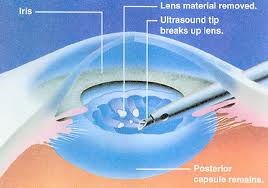

CATARACTOUS LENS BEING BROKEN BY PHACO NEEDLE THROUGH

1 MM to 2.8 MM IN INCISION

What is Phaco emulsification? (Stitch less cataract surgery)

In this surgery the cataractous lens is broken down into small pieces with the help of ultra sound energy and sucked out. The operation is done through a < 1 mm to 2.8 mm small tunnel incision so that after operation no stitches are required because incision is self sealing. Intra ocular lens is also implanted through the same incision. The foldable lenses are used these days. These lenses get folded and are loaded in a plastic injection. The lens is then injected into the eye through the small incision made for surgery.